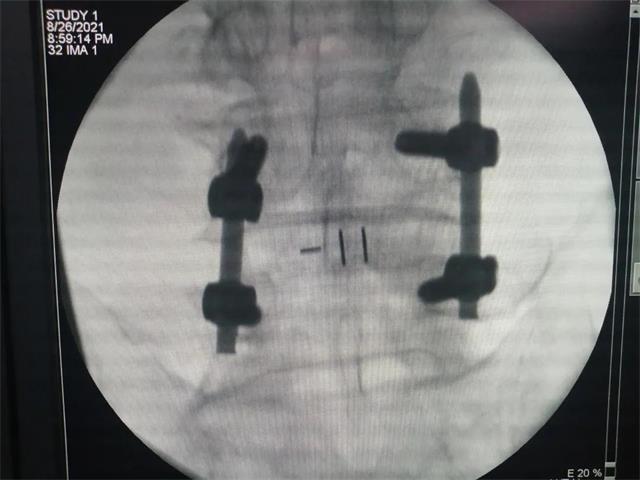

机器人经皮置钉

术后影像